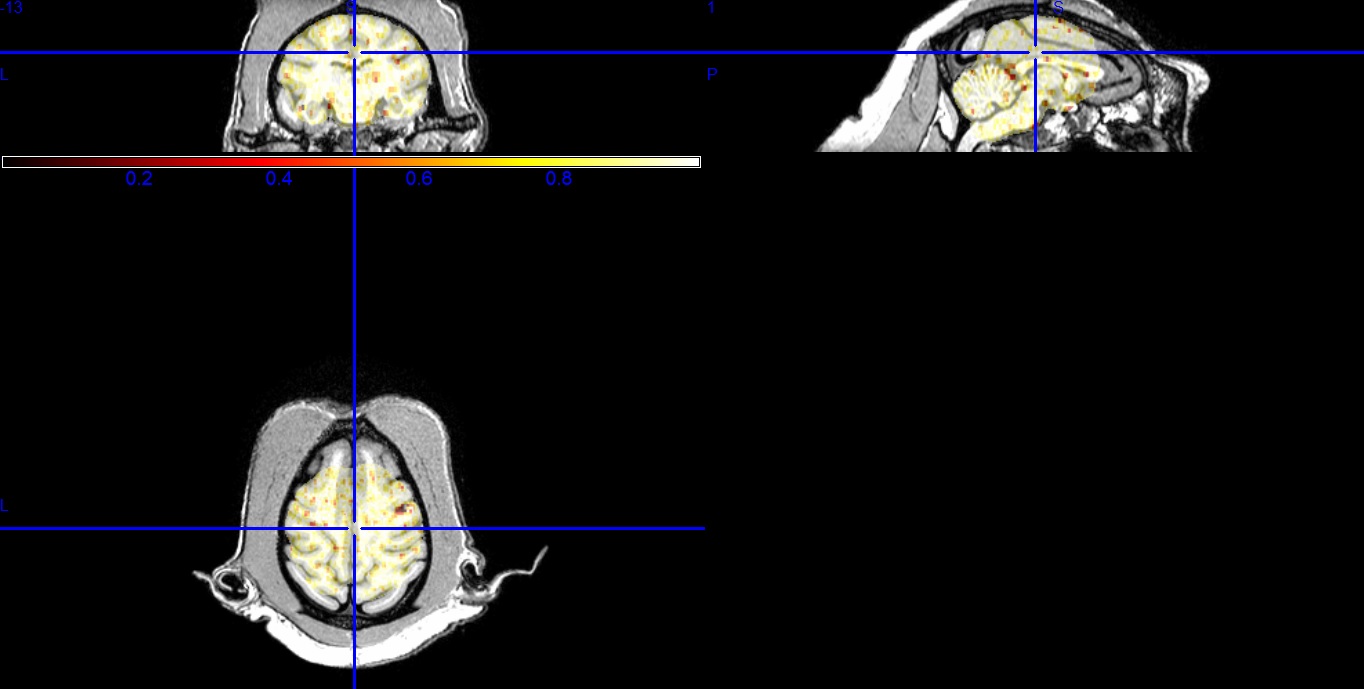

is that this step has been already performed if I am using Conn14p. I am attaching my results as a jpeg image. According to the convention, it should be the regions with least p value that are most likely to be correlated with my ROI. So the red regions are the best correlated areas?